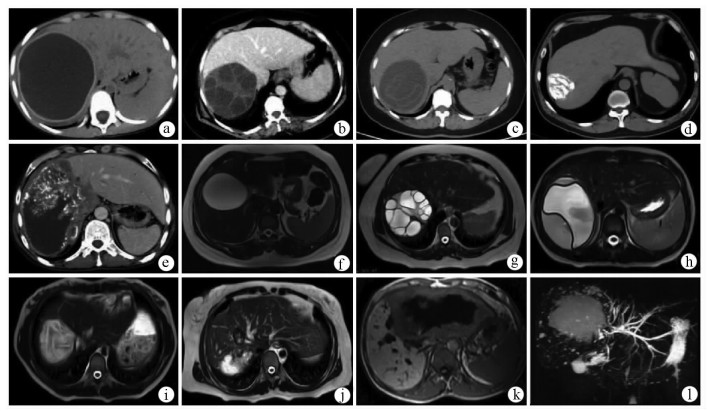

Expert consensus on the imaging diagnosis of hepatic echinococcosis

Radiology of Infection Sub-branch, Radiology Branch, Chinese Medical Association, Committee on Radiology of Infectious, Radiology Branch, Chinese Medical Doctor Association

2021, 37(4): 792-797. DOI: 10.3969/j.issn.1001-5256.2021.04.014

Abstract(1370) HTML (648) PDF (2065KB)(146)

Abstract:

Echinococcosis is a zoonotic disease with global distribution and has become an issue seriously affecting public health around the world. Imaging technology plays an important role in the early diagnosis, preoperative evaluation, and treatment outcome monitoring of hepatic echinococcosis. At present, no consensus has been reached on the imaging diagnosis of echinococcosis, which brings difficulties in the learning and training of imaging professionals and the standard diagnosis and treatment of echinococcosis in clinical practice. For this reason, Beijing YouAn Hospital, Capital Medical University, and The First Affiliated Hospital of Xinjiang Medical University organized the radiologists engaged in infection and inflammation from several hospitals to reach a consensus on the basis, principles, and criteria for the imaging diagnosis of echinococcosis and the differential diagnosis of echinococcosis, with reference to international guidelines, related articles, the latest research findings in China and globally, and the methodological requirements for the establishment of guidelines and standards in evidence-based medicine, so as to provide a clear diagnostic basis for clinicians in the clinical application of hepatic echinococcosis imaging.